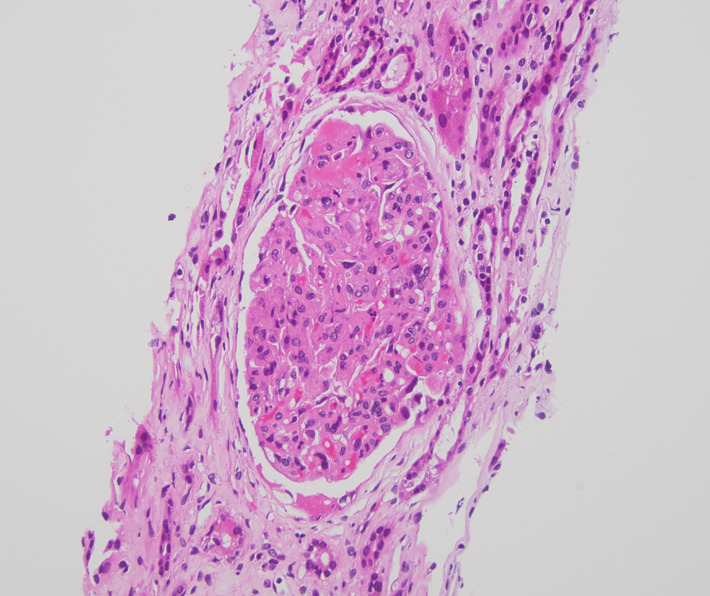

The following day, hemoglobin decreased to 8.8 g/dL and platelets to 53 ×10^3/µL. Direct antiglobulin (Coombs) testing was negative. ANA testing was negative and complement C3/C4 levels were within reference ranges. Peripheral smear demonstrated schistocytes. Hematology assessed a low likelihood of TTP given a PLASMIC score of 3 and ADAMTS13 activity of 51% (not severely reduced). Given persistent AKI with suspected TMA, the nephrology team proceeded with a right kidney biopsy. Biopsy demonstrated acute thrombotic microangiopathy involving glomeruli and small-to-medium vessels, with tubular atrophy/interstitial fibrosis and severe arterio- and arteriolosclerosis (Figure 1). Key diagnostic findings are summarized in Table 1, and relevant laboratory findings are provided in the supplementary material. Blood pressure normalized with nifedipine 60 mg daily and carvedilol 25 mg twice daily.